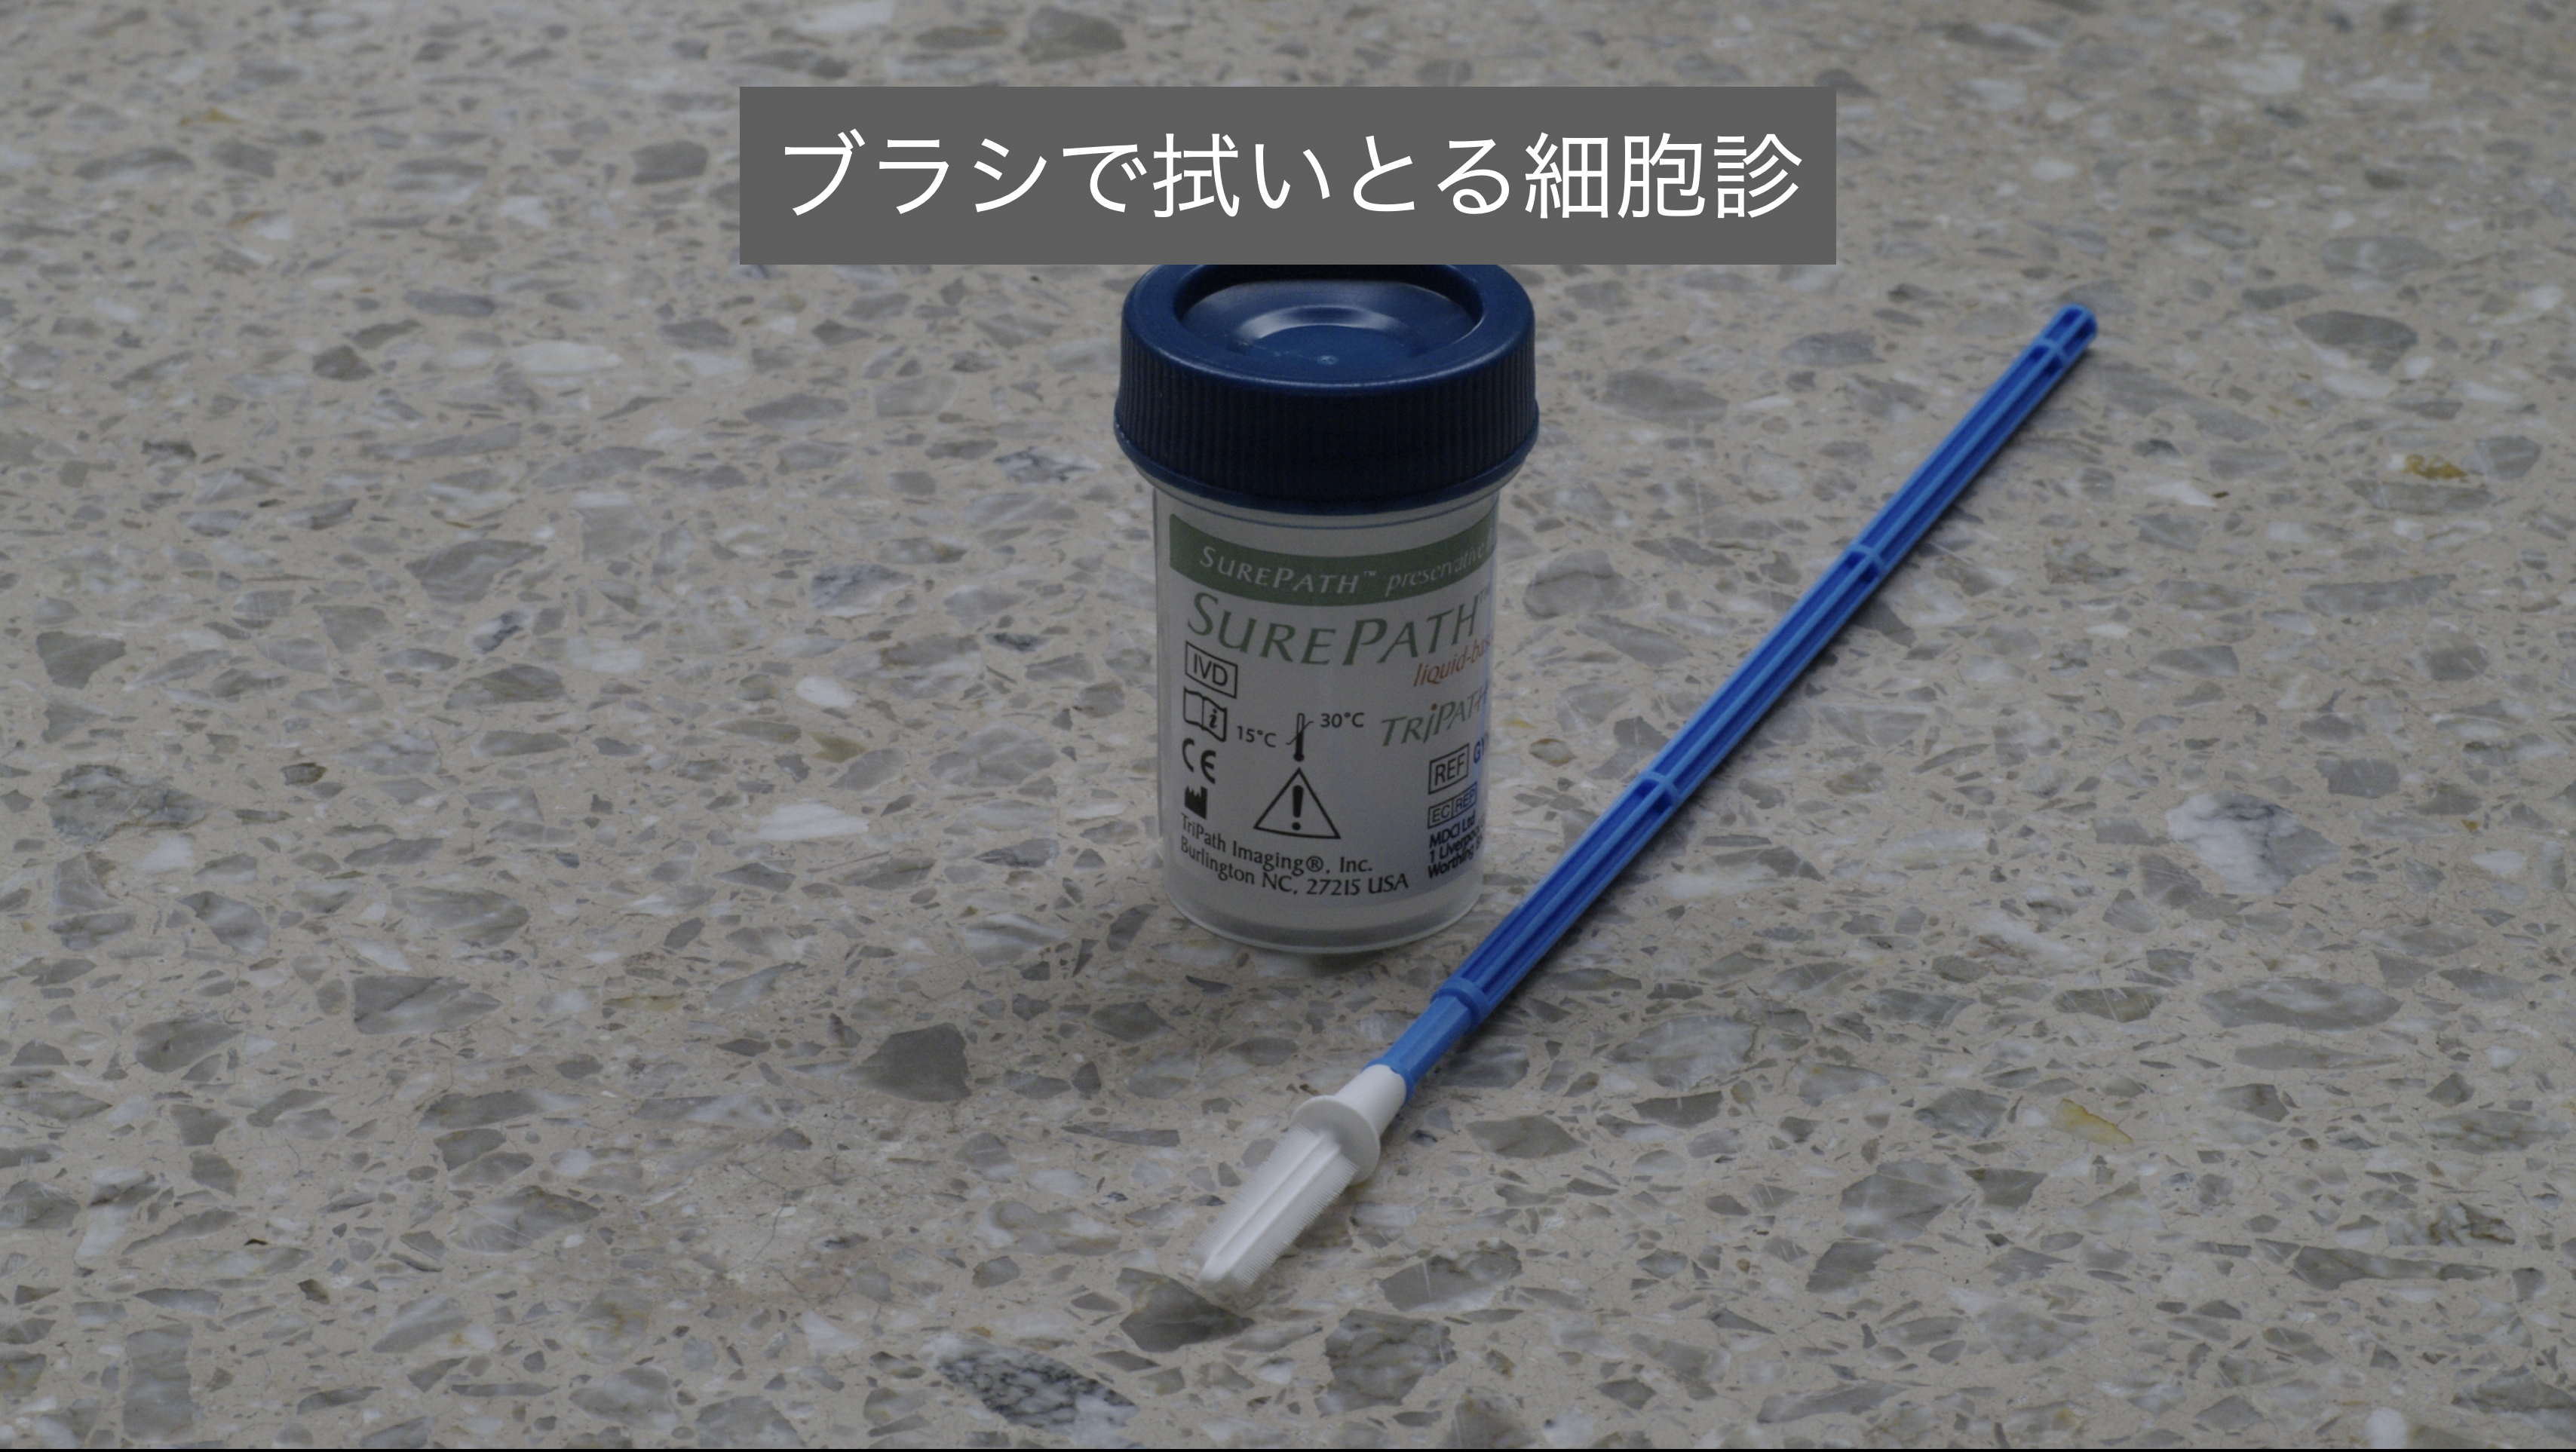

しかし、がんの疑いが、より強く持たれる場合は表面をブラシで拭い取り採取した細胞を病理検査に提出する細胞診や、組織の一部を切除して検査に出す組織診を行ってきました。

ただ診断のためにやむを得ないとはいえ、一般的に行われているこれらの方法は、無用の刺激を細胞に加える事で癌化を促進させる可能性もあり、場合によっては癌細胞を周囲に散らしてしまう危険も否定しきれない手段でもありました。

しかし、がんの疑いが、より強く持たれる場合は表面をブラシで拭い取り採取した細胞を病理検査に提出する細胞診や、組織の一部を切除して検査に出す組織診を行ってきました。

ただ診断のためにやむを得ないとはいえ、一般的に行われているこれらの方法は、無用の刺激を細胞に加える事で癌化を促進させる可能性もあり、場合によっては癌細胞を周囲に散らしてしまう危険も否定しきれない手段でもありました。